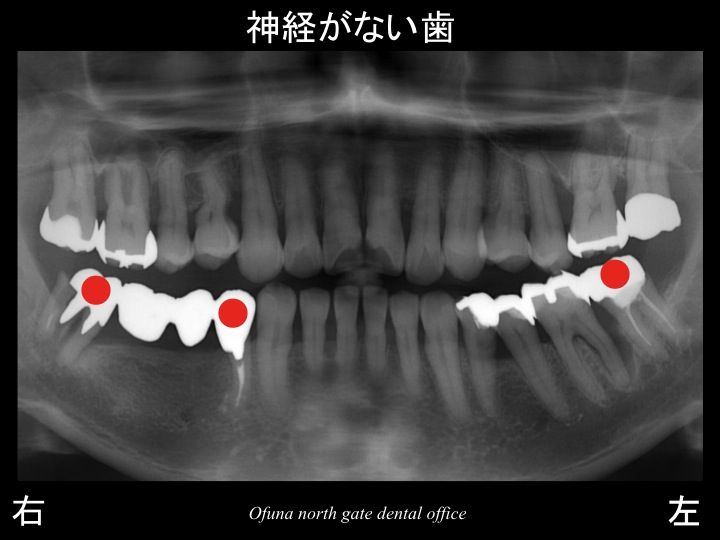

神経のない歯についてはこのブログでもよく紹介してきました。

始めてこのブログを読まれる方のために

簡単に神経のない歯について解説します。

神経のない歯は もろく 通常の咬む力でも割れてしまうことがあります。

神経を取った歯も枯れた木と同じような状態になります。

神経のない歯は血液供給がなくなるためもろくなってしまうのです。

今回歯根破折 した歯以外にも 神経がない歯があります。

こうしたことも考慮して治療計画を立てることが重要です。